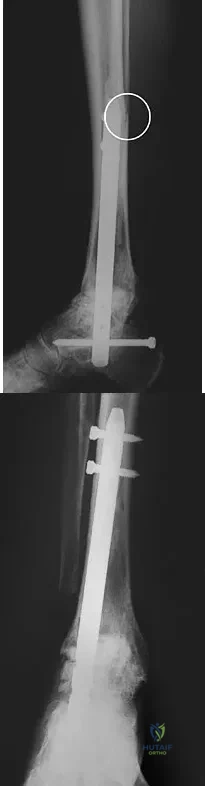

A patient with rheumatoid arthritis with both ankle and subtalar involvement was treated as shown in Figures 11a and 11b. What complication is unique to this type of fixation?